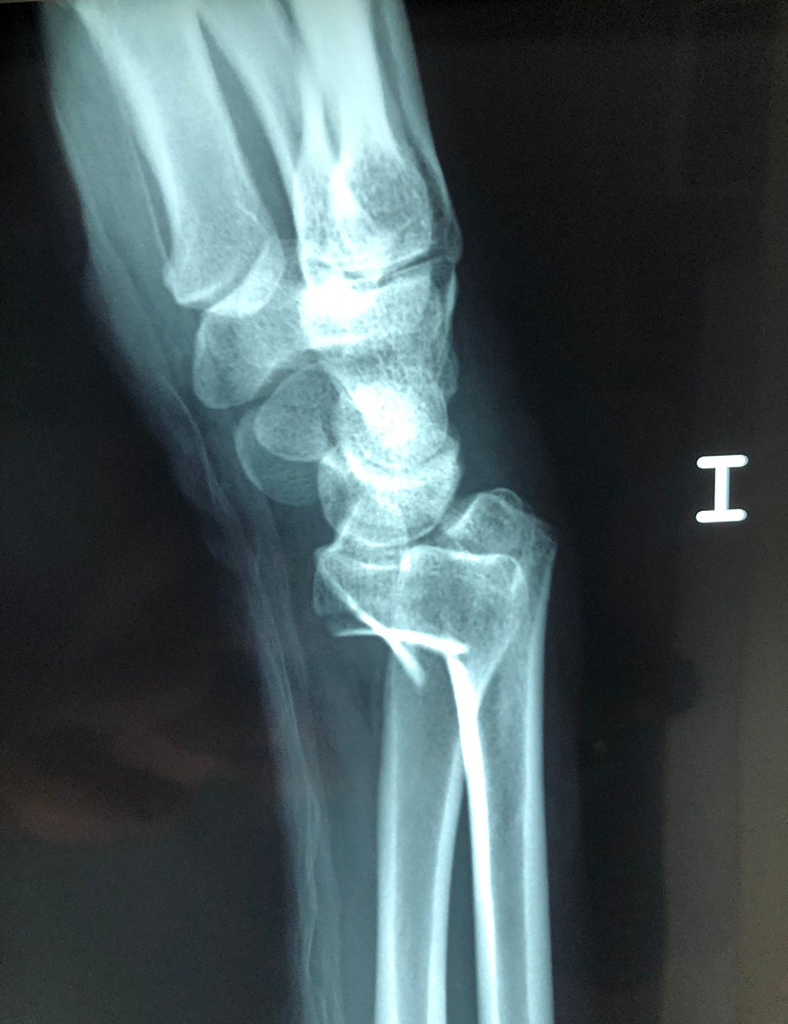

Los procedimientos más comunes en cirugía de la mano son aquellos destinados a reparar traumatismos, incluyendo lesiones de tendones, nervios, vasos sanguíneos, y articulaciones; huesos fracturados; y quemaduras, cortes, y otros daños de la piel.